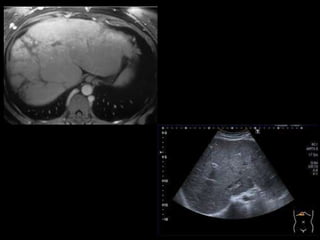

Higado